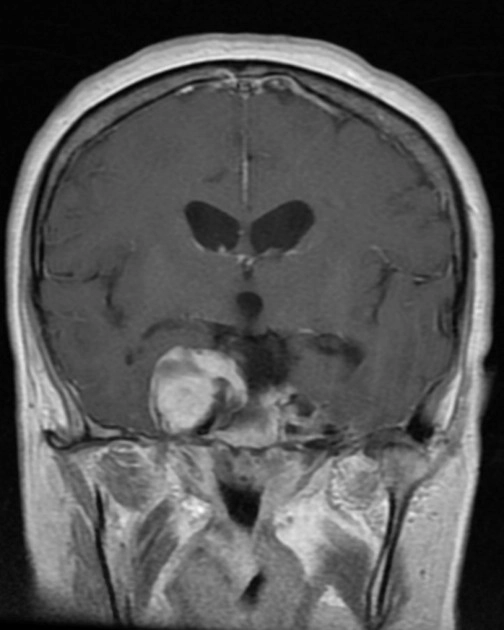

U nguyên bào mạch máu hệ thần kinh trung ương - Hemangioblastoma (central nervous system)

16/03/2026